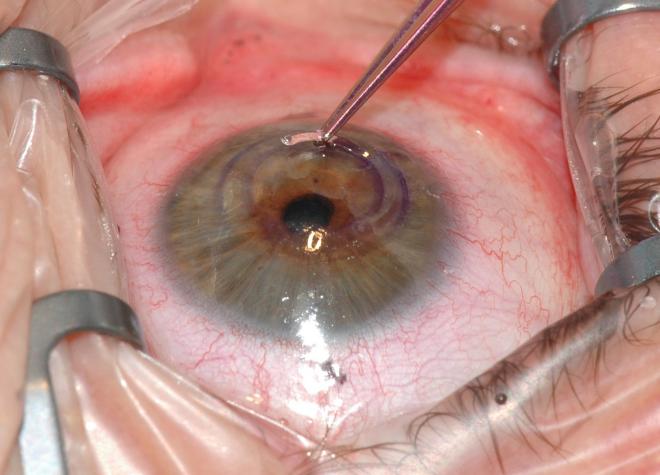

Działanie keraringów polega głównie na spłaszczeniu krzywizny oka. Zabieg ich wszczepienia polega na umieszczeniu przejrzystych, łukowatych implantów z obu stron źrenicy, w utworzonych wcześniej tunelach rogówkowych. Są to specjalne pierścienie śródrogówkowe, których charakterystyczny trójkątny kształt sprawia, że światło padające na nie zostaje odbite na zewnątrz, co pozwala zredukować możliwe pooperacyjne olśnienia. Umiejscowione śródrogówkowo, paracentralnie segmenty powodują zmianę krzywizny zewnętrznej powierzchni rogówki. W efekcie następuje spłaszczenie rogówki, a w przypadku stożka także poprawa jej nieregularności poprzez przemieszczenie szczytu stożka bliżej fizjologicznego centrum rogówki, co wpływa na jakość widzenia.

Bezpieczeństwo metody wszczepiania keraringów potwierdza fakt, że można je dowolnie wymieniać w celu osiągnięcia jak najlepszego efektu. Dużą zaletą tej metody leczenia są też szybkie rezultaty.

Wśród największych korzyści zabiegu wszczepienia keraringów wymienia się poprawę ostrości widzenia, odwracalność (możliwość usunięcia segmentu), brak ingerencji chirurgicznej w centralnej części rogówki, wysoką skuteczność oraz szybką rehabilitację wzrokową (stabilizacja widzenia już nawet po 3 miesiącach). Dla osób, które mają problem ze stożkiem rogówki jest to więc dobre rozwiązanie, pozwalające na długi czas polepszyć jakość widzenia.